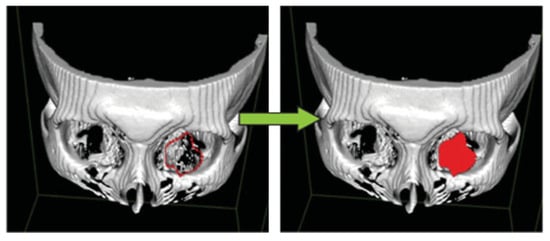

Figure 7.

Connecting all the points of interests allows the surface area of the orbital floor fracture to be measured.

The quantitative aspect of this protocol (Table 2) was modified from a study performed by Schouman et al. []. Using a slice thickness of 2 mm, a total of at least 10 pairs of points of interests were marked in all the coronal images showing the fracture. Three-dimensional (3D) reconstructions of the orbital floor fracture using the 3D Surface Rendering tool are displayed in Figure 7, to illustrate how the surface area of the orbital fracture was obtained. This can also allow the surgeon to visualize the orbital defect and assist in the creation of a personalized preformed orbital implant if surgery is necessary to reconstruct the defect.